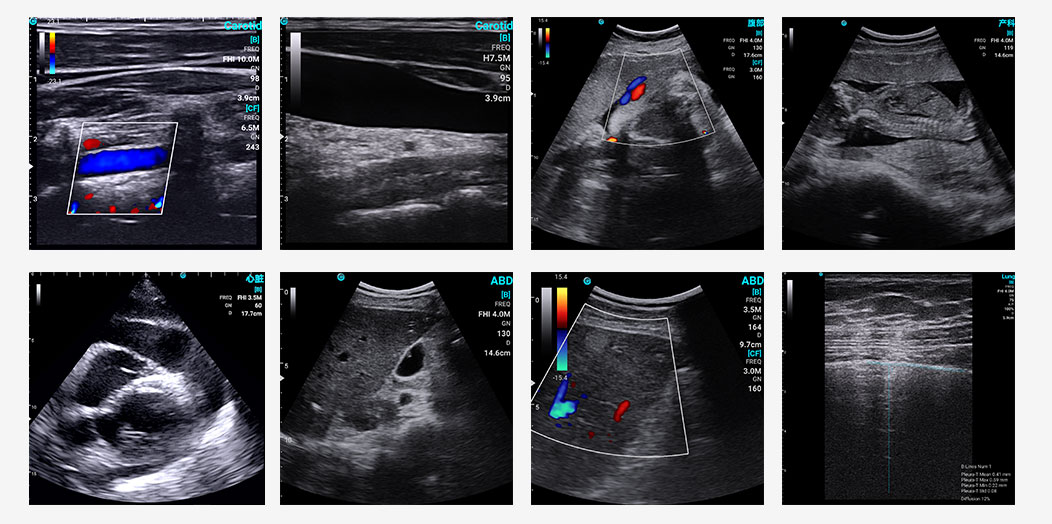

Exemplary sonographic images of SonoEye in B mode, C mode

?